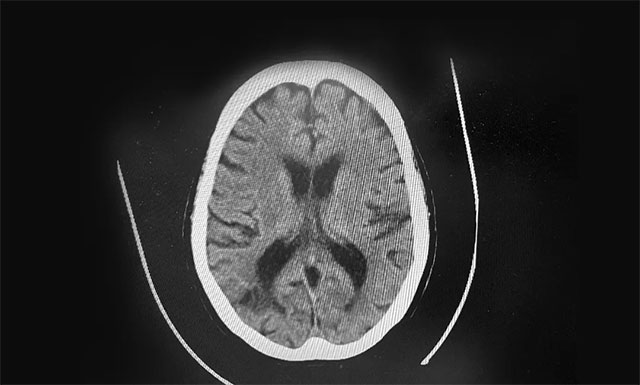

▲ 根据急诊CT影像结果,排除患者脑出血

19:37 患者头部CT检查完成,影像科3分钟出报告,CT报告排除患者脑出血。根据影像学检查结果,并结合其病史,张琪主任判断患者为急性脑梗,发病时间为18:00分左右,还处于静脉溶栓治疗4.5小时的时间窗内,有溶栓治疗指征,可溶栓治疗,积极治疗血管有再通希望。